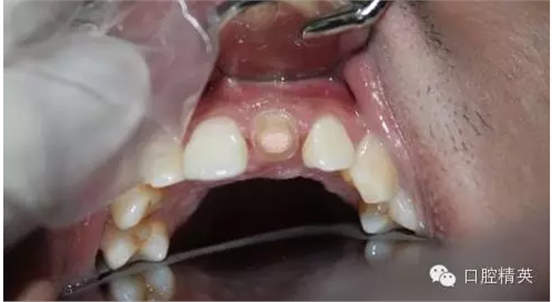

一年輕小伙,在打籃球中,被隊(duì)友打斷門牙,來(lái)本診所時(shí)已經(jīng)露髓,局麻拔髓后,行RCT。后因經(jīng)濟(jì)關(guān)系,擬鈷鉻樁加鈷鉻烤瓷冠修復(fù),備牙后才留照片:

1:牙根,備牙后,